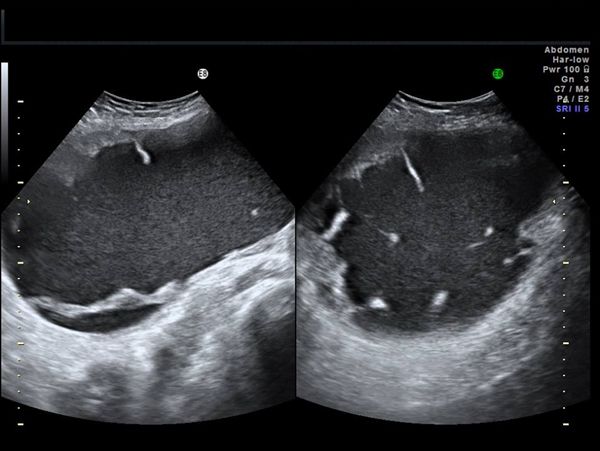

What is your diagnosis based on these images of the fetal heart?